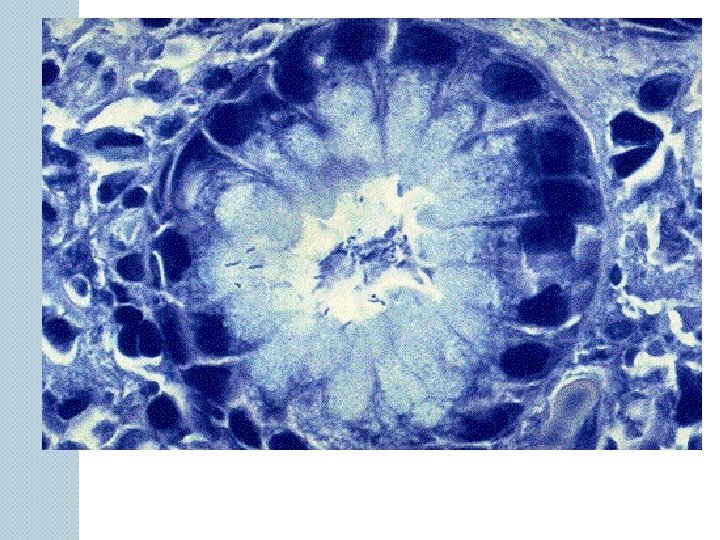

Cirrhosis represents the end stage of chronic liver disease in which much of the functional liver tissue has been replaced by fibrous tissue. It is characterized by diffuse fibrosis and conversion of normal liver architecture into structurally abnormal nodules. The disruption of vascular channels predisposes to portal hypertension and its complications; obstruction of biliary channels and exposure to the destructive effects of bile stasis; and loss of liver cells, leading to liver failure.

Pathophysiology of The Cirrhotic Liver Cirrhosis is final stage of many types of liver injury Appearance of cirrhotic liver varies Early - liver is large and fatty Later - scar tissue forms, liver becomes small and rough Blood flow through liver is compromised Dams up in spleen and G. I. tract Organs become congested and can’t function properly